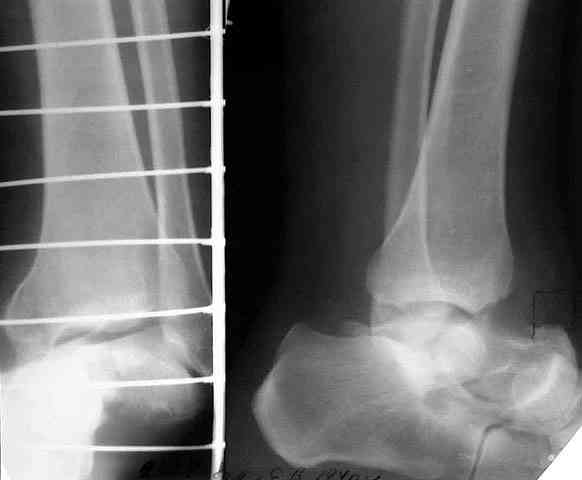

> кости. Выполнена ПХО, фиксация голени и стопы стержневым аппаратом.

> Рана зажила без осложнений. Аппарат демонтирован через 1,5 месяца.

> В настоящее время больной предъявляет жалобы на боль в